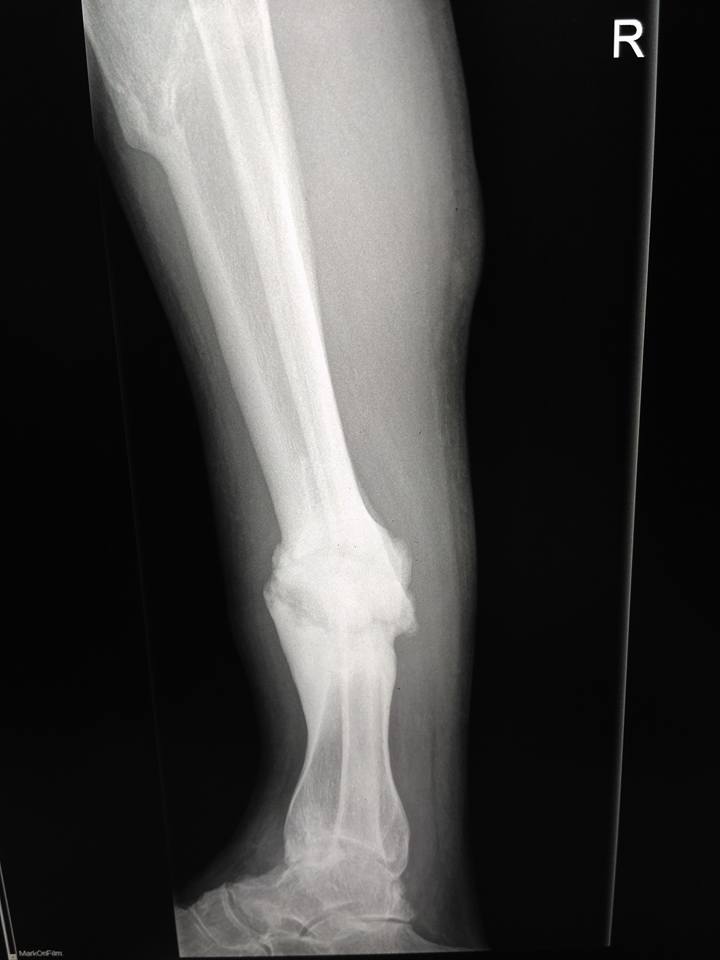

[Ortho] Псевдартроз tibia с варусной деформацией

Пациент мужчина 40 лет. Около 2-х лет назад травма. Лечили со слов

пациента гипсом, не было страховки, прописки и все было отягощено

хр.алкоголизмом.

Сейчас пациент встал так сказать на путь истинный, не пьет больше года,

выправил документы и хочет прямую ногу.

В области перелома в нижней трети подвижности практически нет, нога опорная.

Коллеги, какие мнения? Вопрос, стоит ли попытаться одномоментно

исправить ситуацию стержнем или растянуть сразу не удастся? Стоит ли

делать коррекцию в верхней трети?